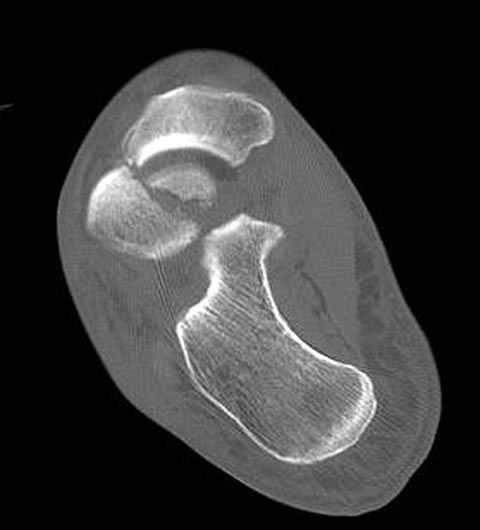

В декабре у меня был пациент с политравмой и аналогичным повреждением тарана с подвывихом в таранно- ладьевидном суставе, единственное отличие - отломок головки тарана был меньше по размеру и фрагментирован, поэтому его фиксация была невозможна.

Для доступа к задне-медиальному суставному фрагменту я выполнил косую остеотомию внутренней лодыжки у её основания -получается хороший доступ к голеностопу, адекватный обзор и возможность восстановить суставную поверхность. фрагмент фиксировал двумя 3,5 мм спонгиозными винтами с неполной резьбой, *утопив* головки винтов в кость. Аналогичная фиксация и двумя тягловыми винтами и внутренней лодыжки. \в качестве альтернативы для

фиксации фрагмента тарана можно было бы использовать и герберт винты, но по организационным причинам :-(( набора не оказалось под рукой).

Вывих в таранно-ладьевидном суставе удалось вправить с помощью Howard retractor, используя его в качестве рычага.Сегодня искал в рентген архиве

Повторный осмотр назначил через 2 мес с момента операции. Отдаленных наблюдений такого подхода у меня нет( достаточно редкий тип повреждений таранаHawkins II), но наблюдения в ближайшем послеоперационном периоде выглядели вполне прилично, на мой взгляд.